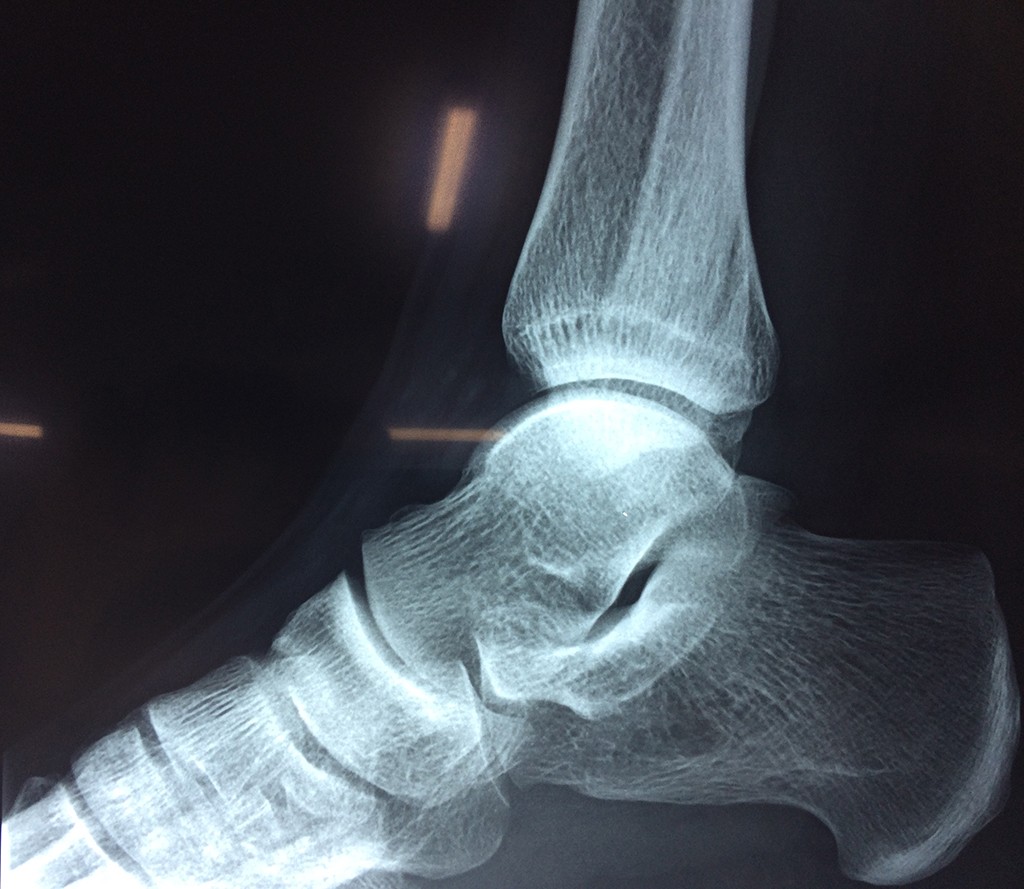

Una fractura de tobillo es la rotura de uno o más de los huesos del tobillo. Estas fracturas pueden ser:

Algunas fracturas de tobillo pueden requerir cirugía si: